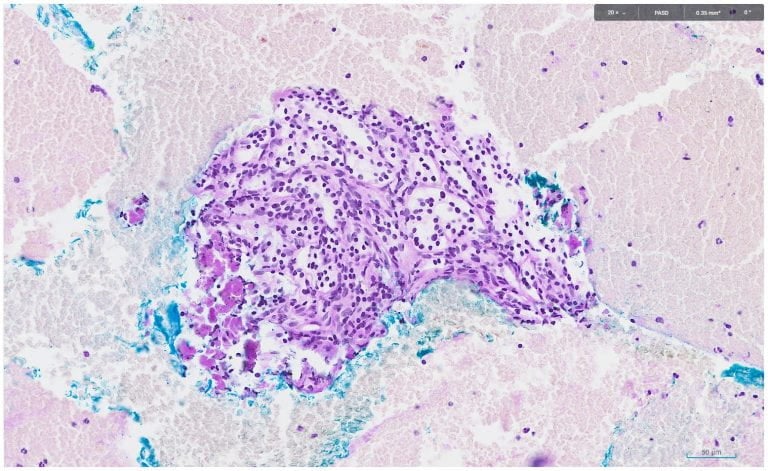

PAS and DPAS staining showed the following:

The overall cyto-histo-morphology and immuno-histochemical findings favour a diagnosis of serous cystadenoma.